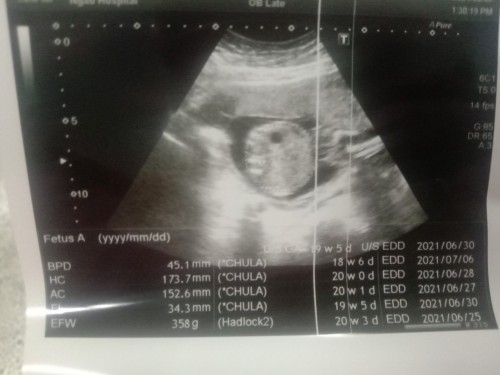

ศีรษะค่ะ ถ้าเห็นเเค่กลมๆ ถ้าท้องจะเห็นทั้งตัว

หัวค่ะ ที่เป็นรูน่าจะกระหม่อม ค่ะ

ท้องค่ะ ตรงดำๆกลมๆคือกระเพาะ

เค้าว่าเป็นช่วงท้อง นะคะ

คิดว่าน่าจะท้องค่ะ

น่าจะส่วนศีรษะค่ะ

ศีรษะเด็ก

กลมๆ หัวค่ะแม่